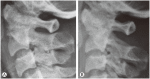

Methods: Upper cervical lesions in nine patients undergoing hemodialysis were surgically treated. Mean age at surgery was 61.6 years (range, 52-68 years), and the mean follow-up period was 45.4 months (range, 2-98 months). Patients had undergone hemodialysis for an average of 25.3 years (range, 16-40 years) at surgery. Seven patients with destructive spondyloarthropathy (DSA) of the upper cervical spine were treated with atlantoaxial or occipitocervical fixation. Two patients with retro-odontoid pseudotumors were treated with C1 posterior arch resection alone. Japanese Orthopedic Association (JOA) scores for cervical myelopathy, postoperative complications, postoperative radiography, and preoperative and postoperative occipital pain were evaluated.

Results: Mean preoperative and postoperative JOA score was 3.7 and 8.1, respectively. The seven patients with DSA had severe preoperative occipital pain that disappeared postoperatively. Postoperative radiography showed solid bone union in DSA cases and no instability in pseudotumor cases.